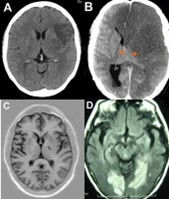

Se realiza un estudio en el que se halla la relación entre la depresión post-ictus y la lesión en el hemisferio cerebral izquierdo, localizando las lesiones propias de la depresión en las regiones corticales, frontal y dorsolateral izquierda, y ganglios basales.

Estudios posteriores afirman esta hipótesis y determinan que aquellos pacientes con las lesiones en el lóbulo fronto-lateral izquierdo poseen mayor probabilidad de tener depresión durante el período post-ictus agudo que aquellas personas que presentan lesiones similares pero que se daban en el lado derecho. No obstante, no existen estudios suficientes que hayan podido verificar esta hipótesis. Por todo ello, no se han encontrado las evidencias necesarias para poder determinar una relación entre la lateralización del ictus y el riesgo de presentar depresión. Sin embargo, una de las estructuras que sí se ha llegado a definir como propia de la depresión es la amígdala, la cual está implicada en la regulación del humor y emociones.

Posteriormente, se concluye que los pacientes que habían pasado por un ictus o un accidente isquémico transitorio (AIT) tenían una amígdala de menor tamaño y eran los que principalmente podían tener daño cognitivo.